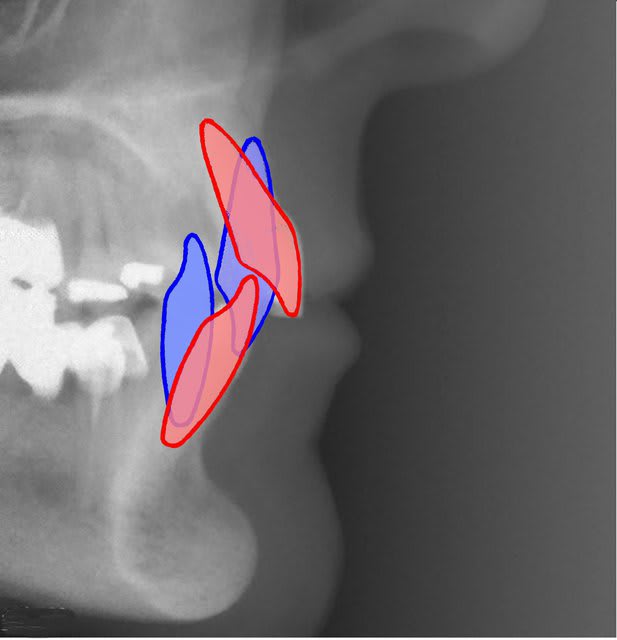

Mon schéma de bio mécanique en page 1 de ce post n'est pas bon pour expliquer le recul de l'apex ?

Voici une images plus explicite. Je crois que les libellules ne sont pas décrites dans l'article que tu cites mais elles le sont d’une manière succincte dans celui que j'ai publié en septembre dernier dans "L'Orthodontie Française". Donne-moi en MP tes coordonnées et je t‘enverrai par mail une planche explicative de leur fabrication, celle qu’on donne quand on fait des TP.

> Mon schéma de bio mécanique en page 1 de ce post n'est pas bon pour expliquer

> le recul de l'apex ?

Si, sauf que ton centre de résistance me semble un peu bas, mais surtout que cela impose un fil excessivement rigide bloqué au niveau molaires pour empêcher la vestibuloversion coronaire. Dans le cas que j’ai montré, le fil était très fin, en NiTi .012 (0,3mm).